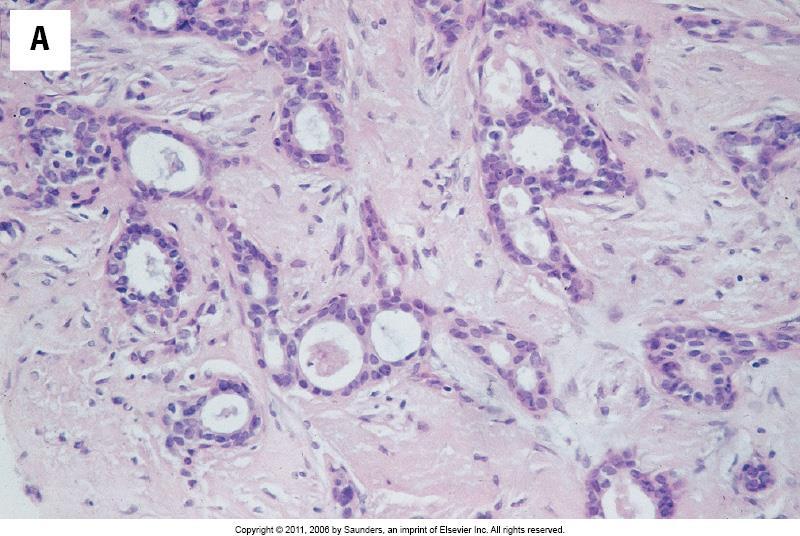

All parts of the tumour are scanned. Clear acinar or gland formation or defined tubular structures with a central luminal space are assessed semi-quantitatively.

Score 1

Score 2

Score 3

Pure tubular carcinomas ± 5% of all invasive breast carcinomas Bland tubules with angulated outline and open lumen Haphazard tubular arrangement in a desmoplastic stroma SMM and p63 negative Good prognosis compared to other invasive ductal carcinoma